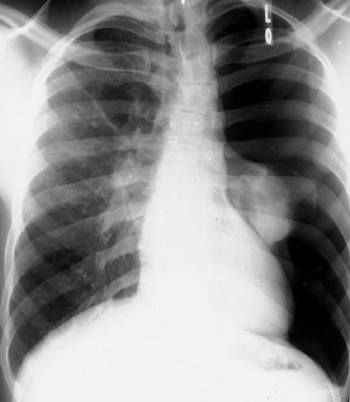

Earliest radiological sign of Pulmonary Venous Hypertension in Chest X-ray is:

Варианты ответов

- Cephalization of pulmonary vascularity

- Pleural effusion

- Kerley B lines

- Alveolar pulmonary edema

CHOOSE A FIGURE FROM FOLLOWINGS, WHERE GIVEN COLLAPSED LUNG

FIG 1

FIG 2

- FIG 1

- FIG 2

- ON BOTH